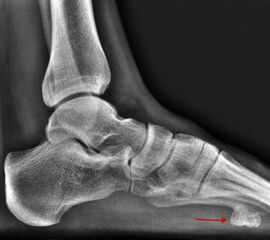

Die juvenile Knochenzyste (Syn. Solitäre Knochenzyste) findet sich am Fuß fast ausschließlich am Calcaneus im Bereich des Ward´schen Dreieckes bzw. im ventralen triangulären Bereich zwischen den Haupttrabekelgruppen (Diard´s Area 6) 3536. Eine physiologische Rarefi­zierung der Trabekelstrukturen in diesem Bereich muss strikt von tumorösen Raumforde­rungen differenziert werden 3738. Die Hauptindikation einer operativen Therapie stellen Schmerzen und eine drohende pathologische Fraktur dar (Abb. 23). Calcaneuszysten, die in der Koronarebene 100% des Querschnitts erreichen oder 30% der Sagittalebene einneh­men, gelten als potentiell frakturgefährdet und sollten auch bei Symptomfreiheit prophylak­tisch operiert werden 3940 (Abb. 24). Da simple Knochenzysten nicht selten als radiolo­gischer Zufallsbefund auffallen, kann auch die Tumorangst des Patienten eine Indikation darstellen. Eine differenzierte Aufklärung des betroffenen Patienten (und seiner Eltern) ist hier umso mehr erforderlich.

Sobald eine osteolytische Knochenläsion des Calcaneus erscheint, ist eine weiterführende Abklärung mittels MRT indiziert. Das intraossäre Lipom des Calcaneus lässt sich im Röntgen nur dann von der simplen Knochenzyste unterscheiden, wenn zentrale, dystrophe Verkal­kungen vorliegen (Abb. 25). Diese auch als Nidus oder Sequestrum bezeichneten Kalzifi­kationen sind typisch, jedoch nicht obligat für das intraossäre Lipom.

Konventionelle Röntgenaufnahmen bleiben in der bildgebenden Diagnostik von Knochen­tumoren das wichtigste diagnostische Werkzeug. Zahlreiche Informationen können hierdurch einfach, kostengünstig und im Vergleich zu einigen alternativen Untersuchungsmethoden strahlungsarm eingeholt werden. Die in der konventionellen Diagnostik eruierbaren und zur weiteren Abklärung erforderlichen Informationen beinhalten Befunde zu Topographie der Läsion (Lokalisation im Fußskelett und im individuellen Knochenbereich), Begrenzungen der Knochenläsion, Art der Osteodestruktion und Periostreaktion, radiologische Erscheinung der Tumormatrix (Zusammensetzung des Tumorgewebes, z.B. dystrophe Verkalkungen) sowie Verhalten und Ausmaß der Weichteilbeteiligung. Dabei sollte der abzubildende Knochen immer einschließlich der benachbarten Strukturen und angrenzenden Gelenke dargestellt werden. Die Röntgenaufnahmen sind stets in mind. zwei Ebenen anzufertigen. In Abhängig­keit der Beschwerden sind belastete Aufnahmen im Stehen anzustreben um zusätzliche Aussagen zur Statik zu erlangen. Die Schrägaufnahme des Fußes stellt eine sinnvolle Ergänzung zu den Standardeinstellungen (dorsoplantar/a.p. und streng lateral) dar um die Knochen des Fußskeletts möglichst überlagerungsfrei darstellen zu können. Ziel- und Spezialaufnahmen können bei Bedarf zusätzlich durchgeführt werden.